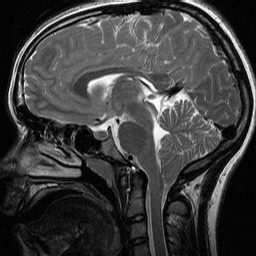

Chiari malformations (CMs) are structural defects in the cerebellum, the part of the brain that controls balance. Normally the cerebellum and parts of the brain stem sit in an indented space at the lower rear of the skull, above the foramen magnum (a funnel-like opening to the spinal canal). When part of the cerebellum is located below the foramen magnum, it is called a Chiari malformation.

CMs may develop when the bony space is smaller than normal, causing the cerebellum and brain stem to be pushed downward into the foramen magnum and into the upper spinal canal. The resulting pressure on the cerebellum and brain stem may affect functions controlled by these areas and block the flow of cerebrospinal fluid (CSF)— the clear liquid that surrounds and cushions the brain and spinal cord—to and from the brain.

Type I involves the extension of the cerebellar tonsils (the lower part of the cerebellum) into the foramen magnum, without involving the brain stem. Normally, only the spinal cord passes through this opening. Type I—which may not cause symptoms—is the most common form of CM and is usually first noticed in adolescence or adulthood, often by accident during an examination for another condition. Type I is the only type of CM that can be acquired.

Type II, also called classic CM, involves the extension of both cerebellar and brain stem tissue into the foramen magnum. Also, the cerebellar vermis (the nerve tissue that connects the two halves of the cerebellum) may be only partially complete or absent. Type II is usually accompanied by a myelomeningocele—a form of spina bifida that occurs when the spinal canal and backbone do not close before birth, causing the spinal cord and its protective membrane to protrude through a sac-like opening in the back. A myelomeningocele usually results in partial or complete paralysis of the area below the spinal opening. The term Arnold-Chiari malformation (named after two pioneering researchers) is specific to Type II malformations.

Type III is the most serious form of CM. The cerebellum and brain stem protrude, or herniate, through the foramen magnum and into the spinal cord. Part of the brain’s fourth ventricle, a cavity that connects with the upper parts of the brain and circulates CSF, may also protrude through the hole and into the spinal cord. In rare instances, the herniated cerebellar tissue can enter an occipital encephalocele, a pouch-like structure that protrudes out of the back of the head or the neck and contains brain matter. The covering of the brain or spinal cord can also protrude through an abnormal opening in the back or skull. Type III causes severe neurological defects.

Magnetic resonance imaging (MRI) is the imaging procedure most often used to diagnose a CM. Like CT, it is painless and noninvasive and is performed at an imaging center or hospital. MRI uses radio waves and a powerful magnetic field to produce either a detailed three-dimensional picture or a two-dimensional “slice” of body structures, including tissues, organs, bones, and nerves. Depending on the part(s) of the body to be scanned, MRI can take up to an hour to complete.